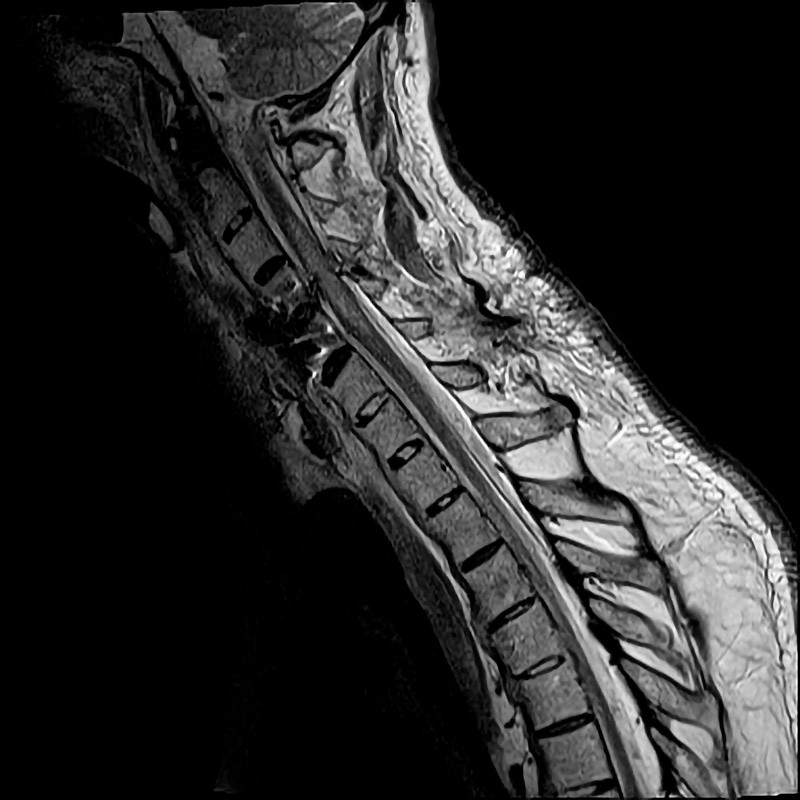

En mann i 70-årene med Bekhterevs sykdom, diabetes type 2 og koronarsykdom ble innlagt på kirurgisk avdeling ved lokalsykehuset etter et fall i en trapp. Ved innkomst til akuttmottak var han bevisst og orientert, men hadde ingen motorisk respons i over- eller underekstremiteter. Det var frie luftveier, regelmessig normofrekvent puls og blodtrykk på 80/60 mm Hg. CT av hodet, nakken, thorax, abdomen og bekkenet etter traumeprotokoll viste en columnafraktur i nivå C4–C5. Etter CT-undersøkelsen ble pasienten ukontaktbar. Blodgassmåling viste respiratorisk acidose, og det var mistanke om hypoventilasjon. Pasienten ble umiddelbart intubert. Supplerende CT caput med angiografi viste ingen tegn til traumatisk blødning, men derimot opphørt sirkulasjon i begge vertebralisarterier med retrograd fylning av bakre cerebrale kretsløp, forenlig med dislokasjon av vertebralisarteriene som følge av columnafraktur. Mannen ble overflyttet til nevrokirurgisk avdeling ved nærmeste regionsykehus og operert på vital indikasjon med reposisjon av cervikal fraktur og osteosyntese. MR av hjernen etter operasjon viste gjenopprettet sirkulasjon i vertebralisarteriene uten gjennomgåtte hjerneinfarkter. MR av ryggmargen viste ryggmargsødem i nivå C2–C5, forenlig med ryggmargsskade (figur 1).